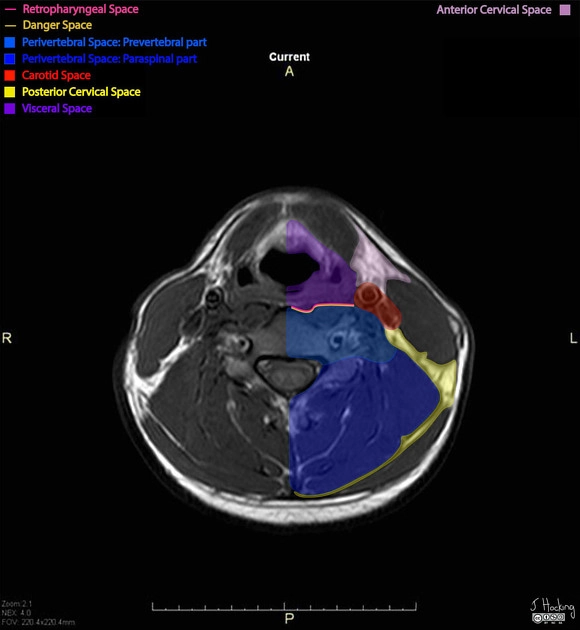

Khoang tạng ở cổ (Visceral space)